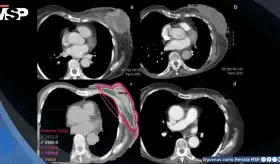

La compresión de la arteria coronaria principal izquierda (LMCA) por dilatación de la arteria pulmonar representa una complicación subdiagnosticada de la hipertensión pulmonar severa, con prevalencia del 6%.